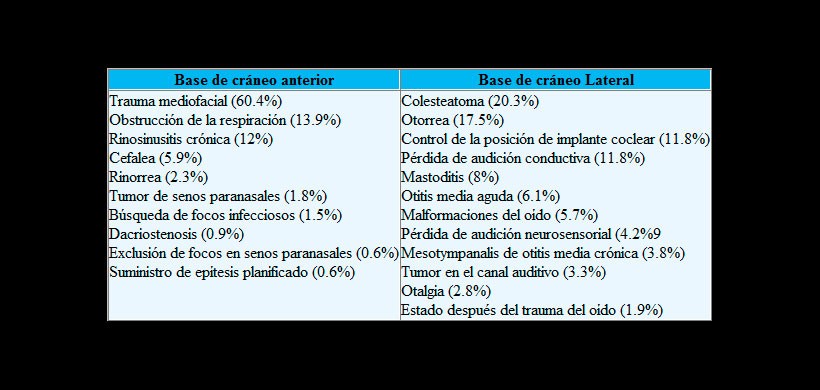

La TCHC es una buena alternativa a la TC convencional como una técnica de imagen de estructuras óseas tanto en niños como en adultos. Las indicaciones más frecuentes para imágenes de la base del cráneo anterior en niños son el traumatismo medio facial, alteraciones en la respiración nasal por obstrucción y la rinosinusitis crónica en comparación con la imagen de la base del cráneo lateral, cuyas indicaciones más frecuentes son el colesteatoma, la otorragia y el control de la posición del implante coclear. En caso de afectación del tejido blando (por ejemplo, complicaciones orbitales / centrales), se debe realizar una resonancia magnética o una TC. Un objetivo debería ser una reducción consiguiente de la exposición a la radiación mediante la indicación adecuada del FOV.

Figura 1: Principales indicaciones de la tomografía computarizada de haz cónico en la especialidad de Otorrinolaringología